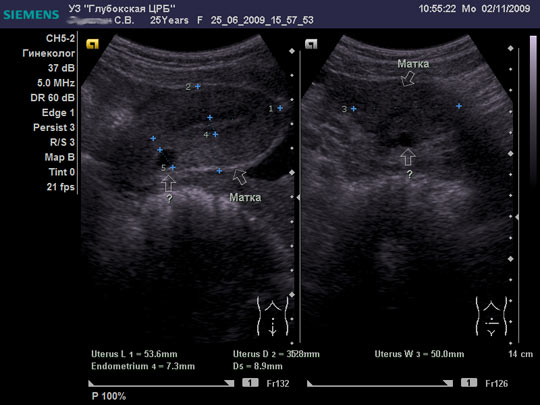

Женщина 25 лет предъявляет жалобы на периодически возникающую болезненность в нижних отделах живота, боли появились около 6-8 мес. Менструальная функция не нарушена. В анамнезе кесарево сечение, ребёнку 2,5 года.

Doc, на взгляд неспециалиста в гинекологическом УЗИ - Nabothian cyst

Я тоже думал про наботовы желёзки, но меня смутил тот момент, что не явилось ли это образование следствием оперированной матки, лигатуры... ну чего-то там с ними... или что-то в этом духе????

Согласен, Наботова или эндо-цервикальная киста шейки. Ничего специфического.

Naboti пишем, эндометриоз в уме

запросто. об эндометриозе надо думать, когда ov.nabotae несколько. и к тому же присутствуют гиперэхогенные линейные включенияDoc писал(а):Спасибо.